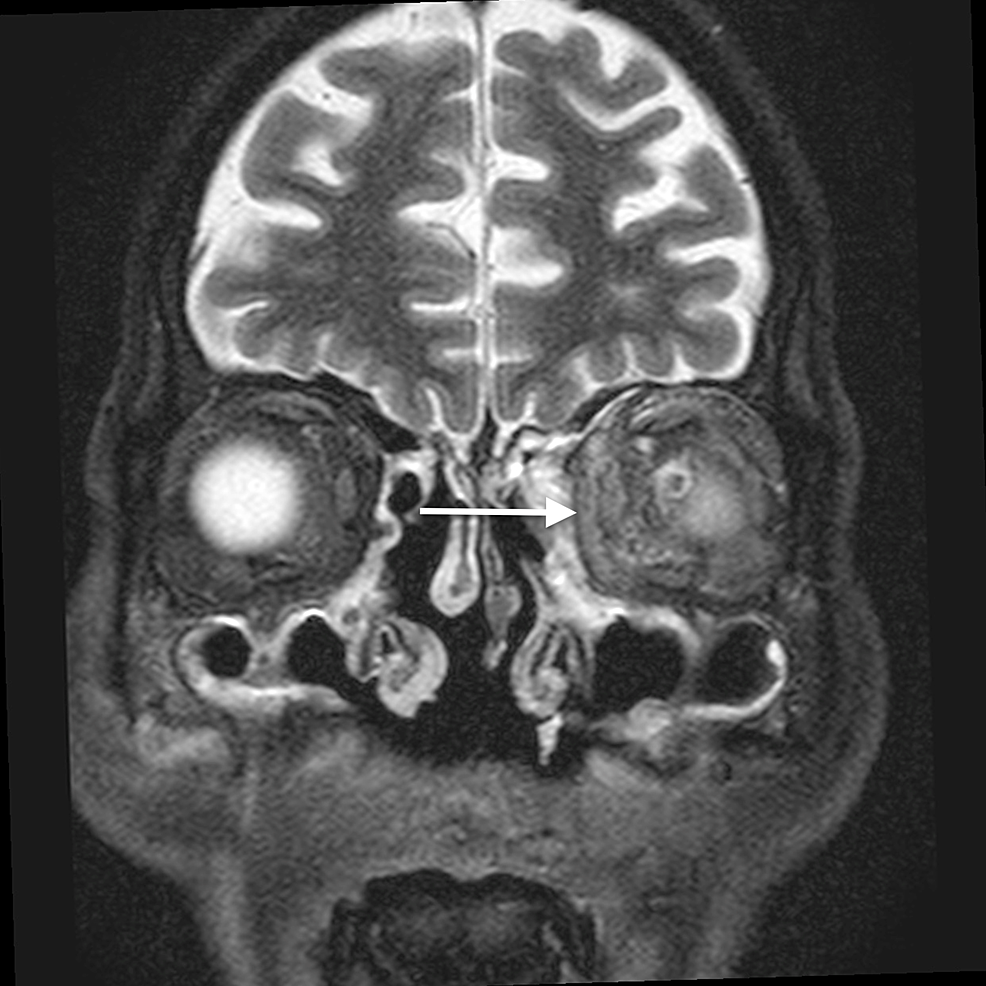

The main complications of orbital cellulitis (Figures 2-4) encountered in our study were:

1. An orbital abscess (Figures 5-6);

2. Preseptal cellulitis and abscess (Figures 7-8);

3. Periorbital cellulitis (Figures 9-10);

4. Dacryoadenitis (Figures 11-12);

5. Optic neuritis/perineuritis (Figure 13);

6. Cavernous sinus thrombophlebitis and thrombosis (Figure 14).

The most common complication of orbital cellulitis was orbital/periorbital abscess formation (eight cases, 53.3%), followed by optic neuritis (four cases, 26.67%), intracranial involvement (four cases, 26.67%), dacryoadenitis (three cases, 20%) and cavernous sinus thrombophlebitis (three cases, 20%).